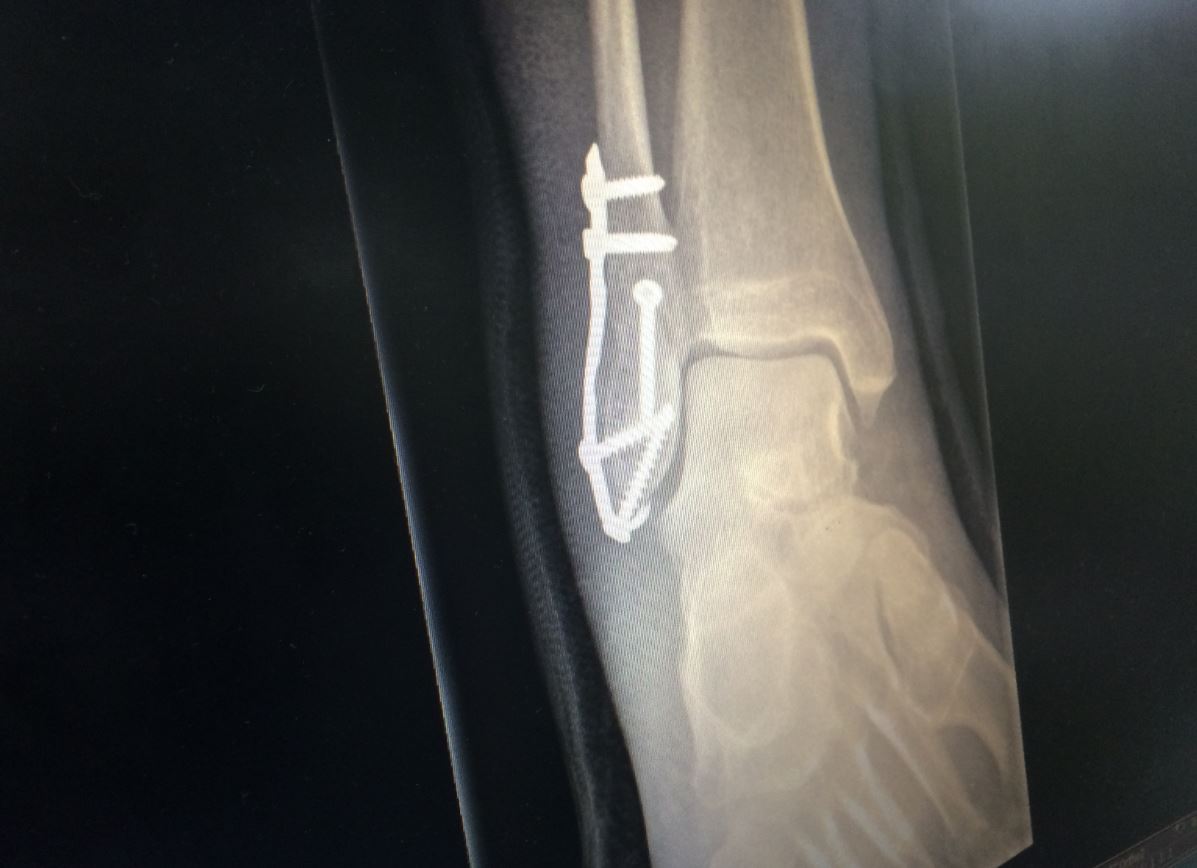

Saturday morning is a competitive time at hospitals due to swarms of junior sports victims, and in fact the three broken bone incidents I’ve experienced (motorbikes currently leading 2-1 over football, with football unlikely to make a comeback as we head into the last quarter) have all been on a Saturday. There was the inevitable long wait because I wasn’t going to die, although when it was my turn the treatment was very competent and the X-ray was conclusive; fractured right fibula. After a few days in plaster, another consultation at the outpatients resulted in surgery the following week to screw the broken bits back together.

I can only assume that the additional three stainless steel screws listed on the surgery manifest that were not in my ankle are now holding the surgeon’s GPS onto the console of his new yacht.

A mere 6½ weeks after the day of infamy, and 5 weeks after the structural fix, the annoying fibreglass boot was removed and the X-rays showed that healing had been achieved. The fibreglass non-weight bearing boot was replaced by a walker fracture boot, however this was only in service for 4 hours before tests clearly showed that it couldn’t safely be used on a standard Triumph brake lever, so was abandoned. The withered state of the leg was a concern, so with a second level Simon Pavey off-road skills training course planned for late October 2015, it was off to the physio for some exercises to try to fatten the calf.